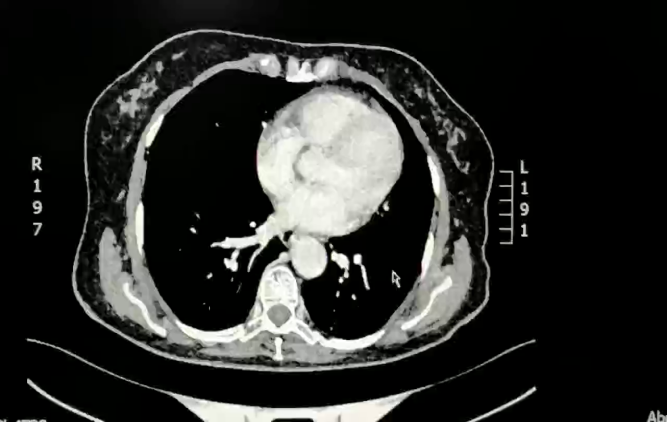

2018-01-23 CT检查示肝S8段边缘部(6-192)见一低密度结节,边界清楚,大小约1.3cm×0.8cm。

2018-07-24 复查CT

肝边缘部见多发低密度结节,边界清楚,大者约2.1cm×l.9cm,未见强化,体积较前增大,数量较前略增多;肝脏边缘结节,体积较前增大,数量较前略增多,提示腹膜种植转移。

2018-07-24 肝MRI:

1.肝S4-8段边缘处多发结节,与前片(2018-05-25)比较,部分体积较前略增大,考虑转移瘤较不典型血管瘤可能性大,建议随访;2.肝S5、S6小结节,转移待排,建议随访。